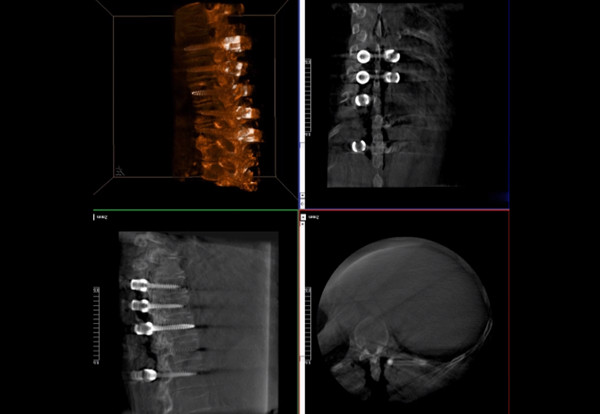

普愛醫(yī)療術(shù)中三維導(dǎo)航C臂快速生成橫斷面、矢狀面、冠狀面斷層圖像和三維立體圖像,方便醫(yī)生確認手術(shù)部位。C形臂的大平板帶來出色的顯示視野,可以更好的顯示手術(shù)部位全局情況,確保手術(shù)規(guī)劃及執(zhí)行的準(zhǔn)確性。

三維影像檢驗螺釘植入效果

一臺C形臂

二維三維影像 皆能完好呈現(xiàn)